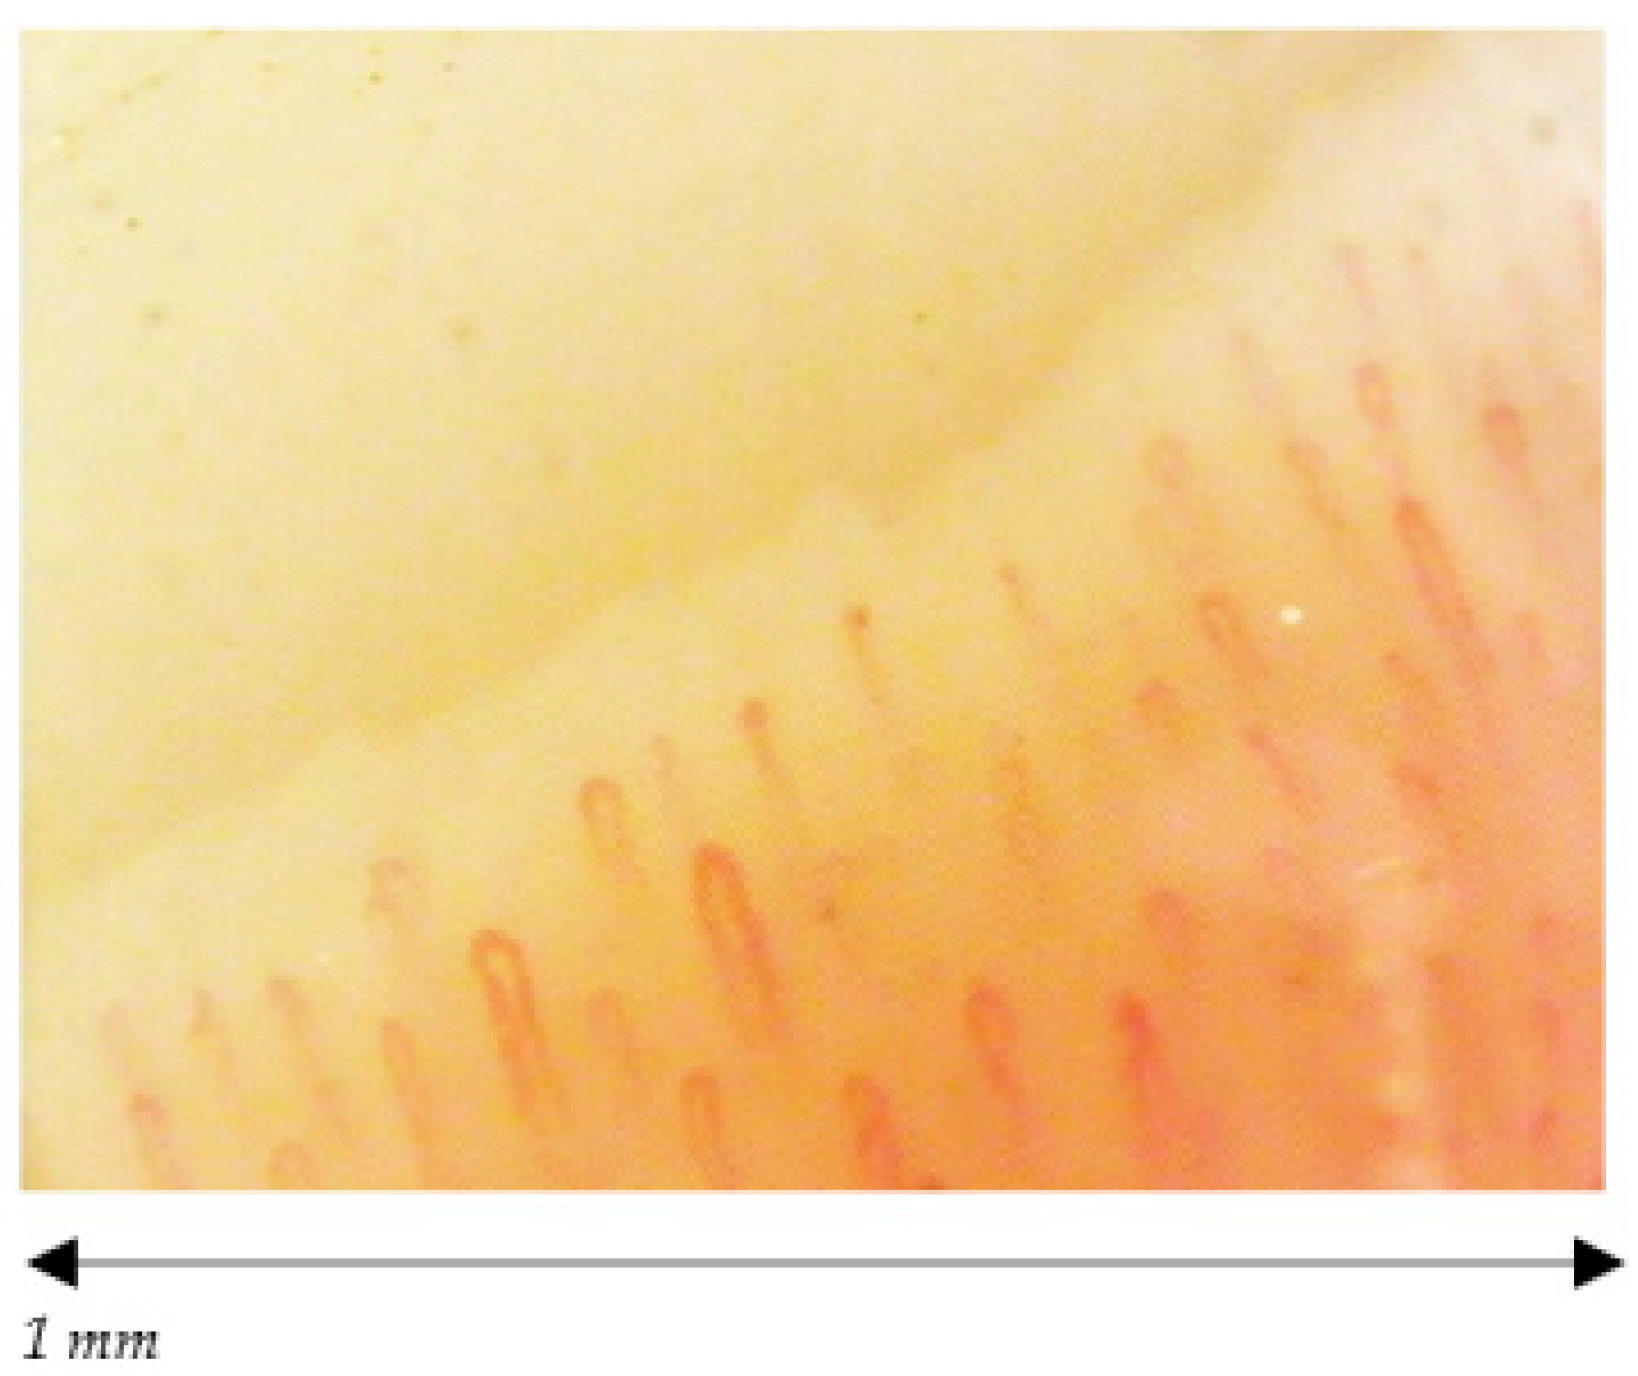

- Cutolo, M.; Sulli, A.; Smith, V. How to perform and interpret capillaroscopy. Best Pract. Res. Clin. Rheumatol. 2013, 27, 237–248. [Google Scholar] [CrossRef]